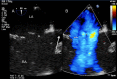

This review article will guide the reader through the basics of echocardiographic assessment of congenital left to right shunts in both paediatric and adult age groups. After reading this article, the reader will understand the pathology and clinical presentation of atrial septal defects (ASDs), ventricular septal defects (VSDs), atrioventricular septal defects (AVSDs) and patent arterial duct. Echocardiography is the mainstay in diagnosis and follow-up assessment of patients with congenital heart disease. This article will therefore describe the echocardiographic appearances of each lesion, and point the reader towards specific features to look for echocardiographically.